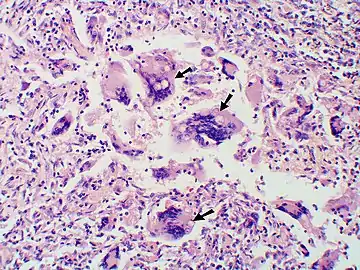

Granuloma with early suppuration. Fungal organisms difficult to recognize at this low magnification.

Large yeast-like fungi seen within giant cells at arrows. Budding yeasts in cytoplasm of giant cells at arrows. Broad-based budding and double contoured cell wall seen in the giant cell in the center is characteristic of Blastomyces dermatitidis.